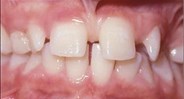

front view left buccal maxillary mandibular

Right Buccal View Frontal View Left Buccal View Maxillary View Mandibular View